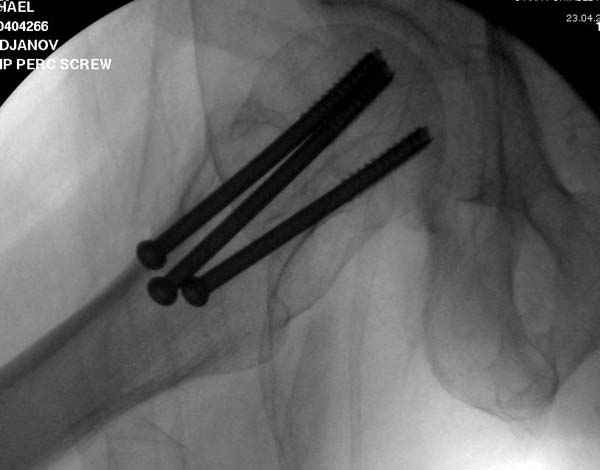

[Ortho] неполный перелом шейки

Профилактику дальнейшего раскола неполного перелома шейки провели тремя канюлированными шурупами.

На второй день после выписки упал дома. Снимки приложены. Коллеги рекомендуют удаление шурупа и вытяжение. Что делать?